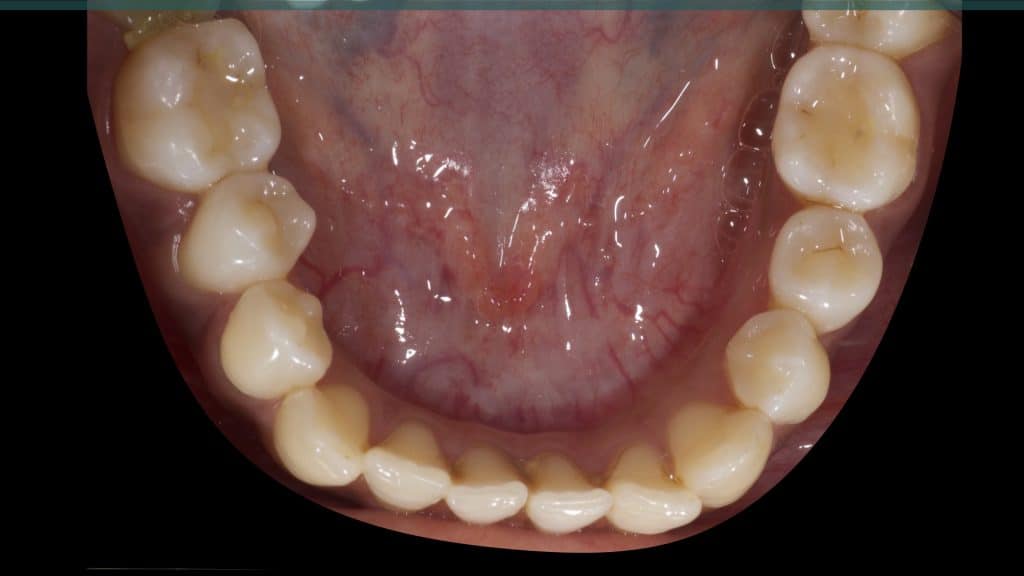

A 27-year female patient with dislodged Resin bonded FPD. She had that FPD for past few years, it had metal wings on palatal surfaces of UR1 and UL2 and a post like metal extension into the root canal of UL1. There was gingival abscess due to fractured root segment most probably due to extended metallic post like structure. Immediate implant placement (IIP) and Immediate restoration (IR) was planned for this patient.